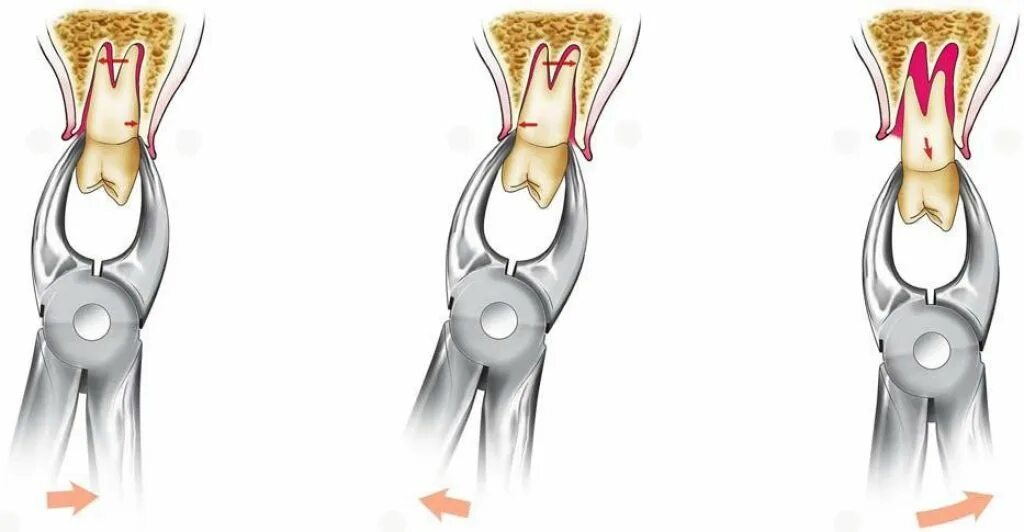

Удалить 7 зуб сверху